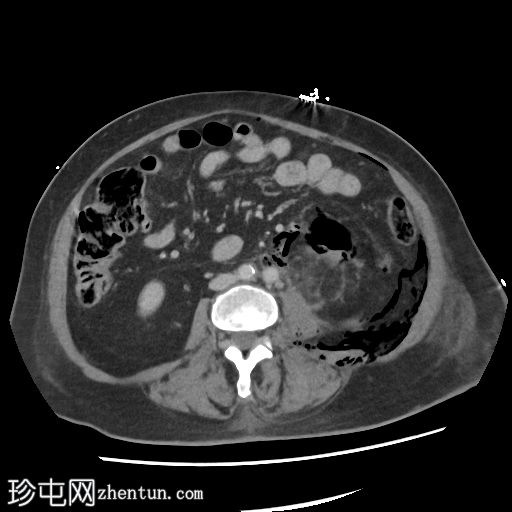

2.jpg

轴位

左肾广泛破坏,伴有碎裂和气体膨胀

气体延伸至:

左侧输尿管;近端输尿管周围有气体包绕,并可见局灶性输尿管周围碎屑/积聚

进入膀胱

沿左肾静脉进入扁平的下腔静脉(脓毒性休克的特征)

沿十二指肠第二段(D2)进入肝门

进入肾周间隙,伴有坏死碎屑

经肾后间隙进入腰大肌、腹膜前脂肪和体壁

进入肠系膜后间隙、肾后间隙、侧圆锥间隙和联合筋膜间隙,直至股鞘

环绕左侧肾上腺、胃和脾脏,并位于膈下

经食管裂孔和主动脉裂孔进入纵隔

腹腔内气体

不对称性皮下炎症